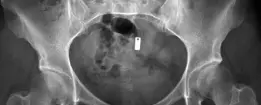

- الأشعة السينية (X-rays): توفر صورًا للعظام وتساعد في تحديد التشوهات الهيكلية مثل خلل التنسج أو الاحتكاك الفخذي الحقي.